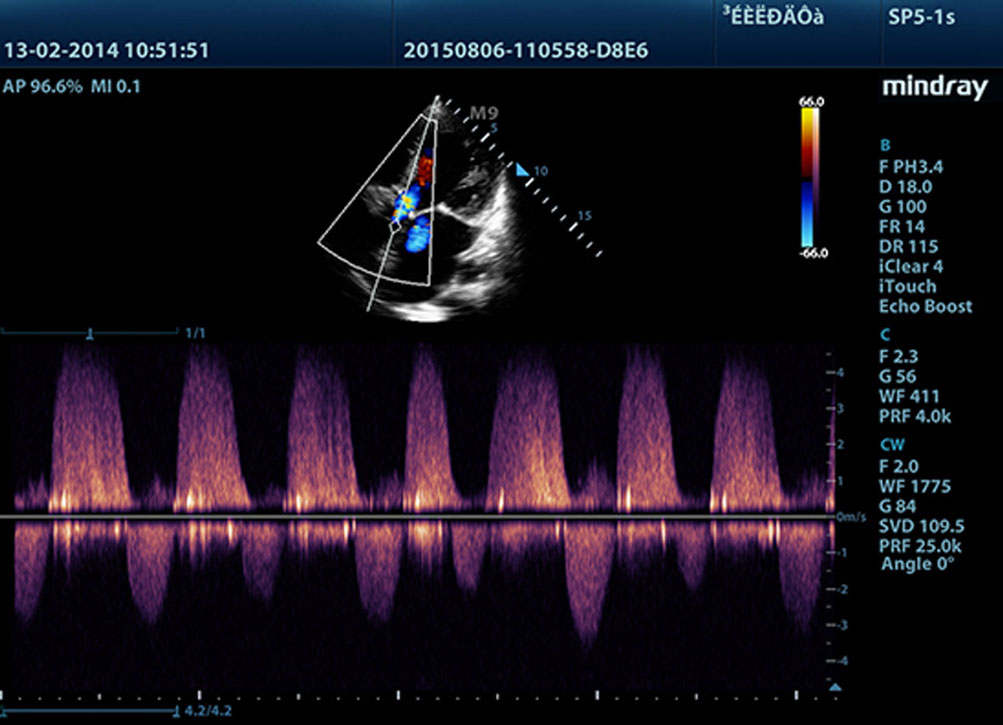

Dank Mindrays Ultraschallplattform der neuen Generation, mQuadro, hat das M9 den Branchenstandard auf ein bislang unbekanntes Niveau gehoben. Fortgeschrittene Signal├╝bertragung und ebensolche Empfangsprozessoren bieten hochsensitive, genaueste Echoerkennung. Innovative Schallkopftechnologie sorgt f├╝r bessere Penetration, h?here Aufl?sung und eine entsprechend einfachere Diagnose.

F├╝r sch?rfere Bilder sind alle mit dem M9 kompatiblen Sonden mit Mindrays einzigartiger 3T-Schallkopftechnologie ausgestattet. Das durch die Einkristalltechnologie verbesserte M9 bietet bessere Penetration und dynamischen Farbfluss, insbesondere bei der Untersuchung schwieriger Patientinnen oder Patienten.

Echo Boost?

Mindrays einzigartige adaptive Signalverarbeitung mit intelligenter Echoerkennung, die zwecks Nutzung der nat├╝rlichen Signal-zu-Rauschen-Information zur Verst?rkung der schwachen Echosignale bei gleichzeitiger Unterdr├╝ckung der diversen Umgebungsger?usche entwickelt wurde, liefert eine ausgeglichenere Brillanz der Bilder und eine verbesserte Visualisierung der Gewebsschichten des Myokards.